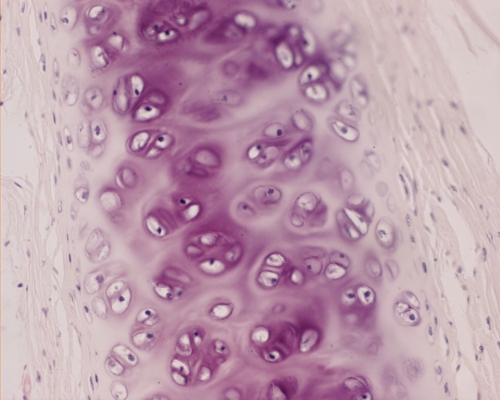

Hyaline cartilage